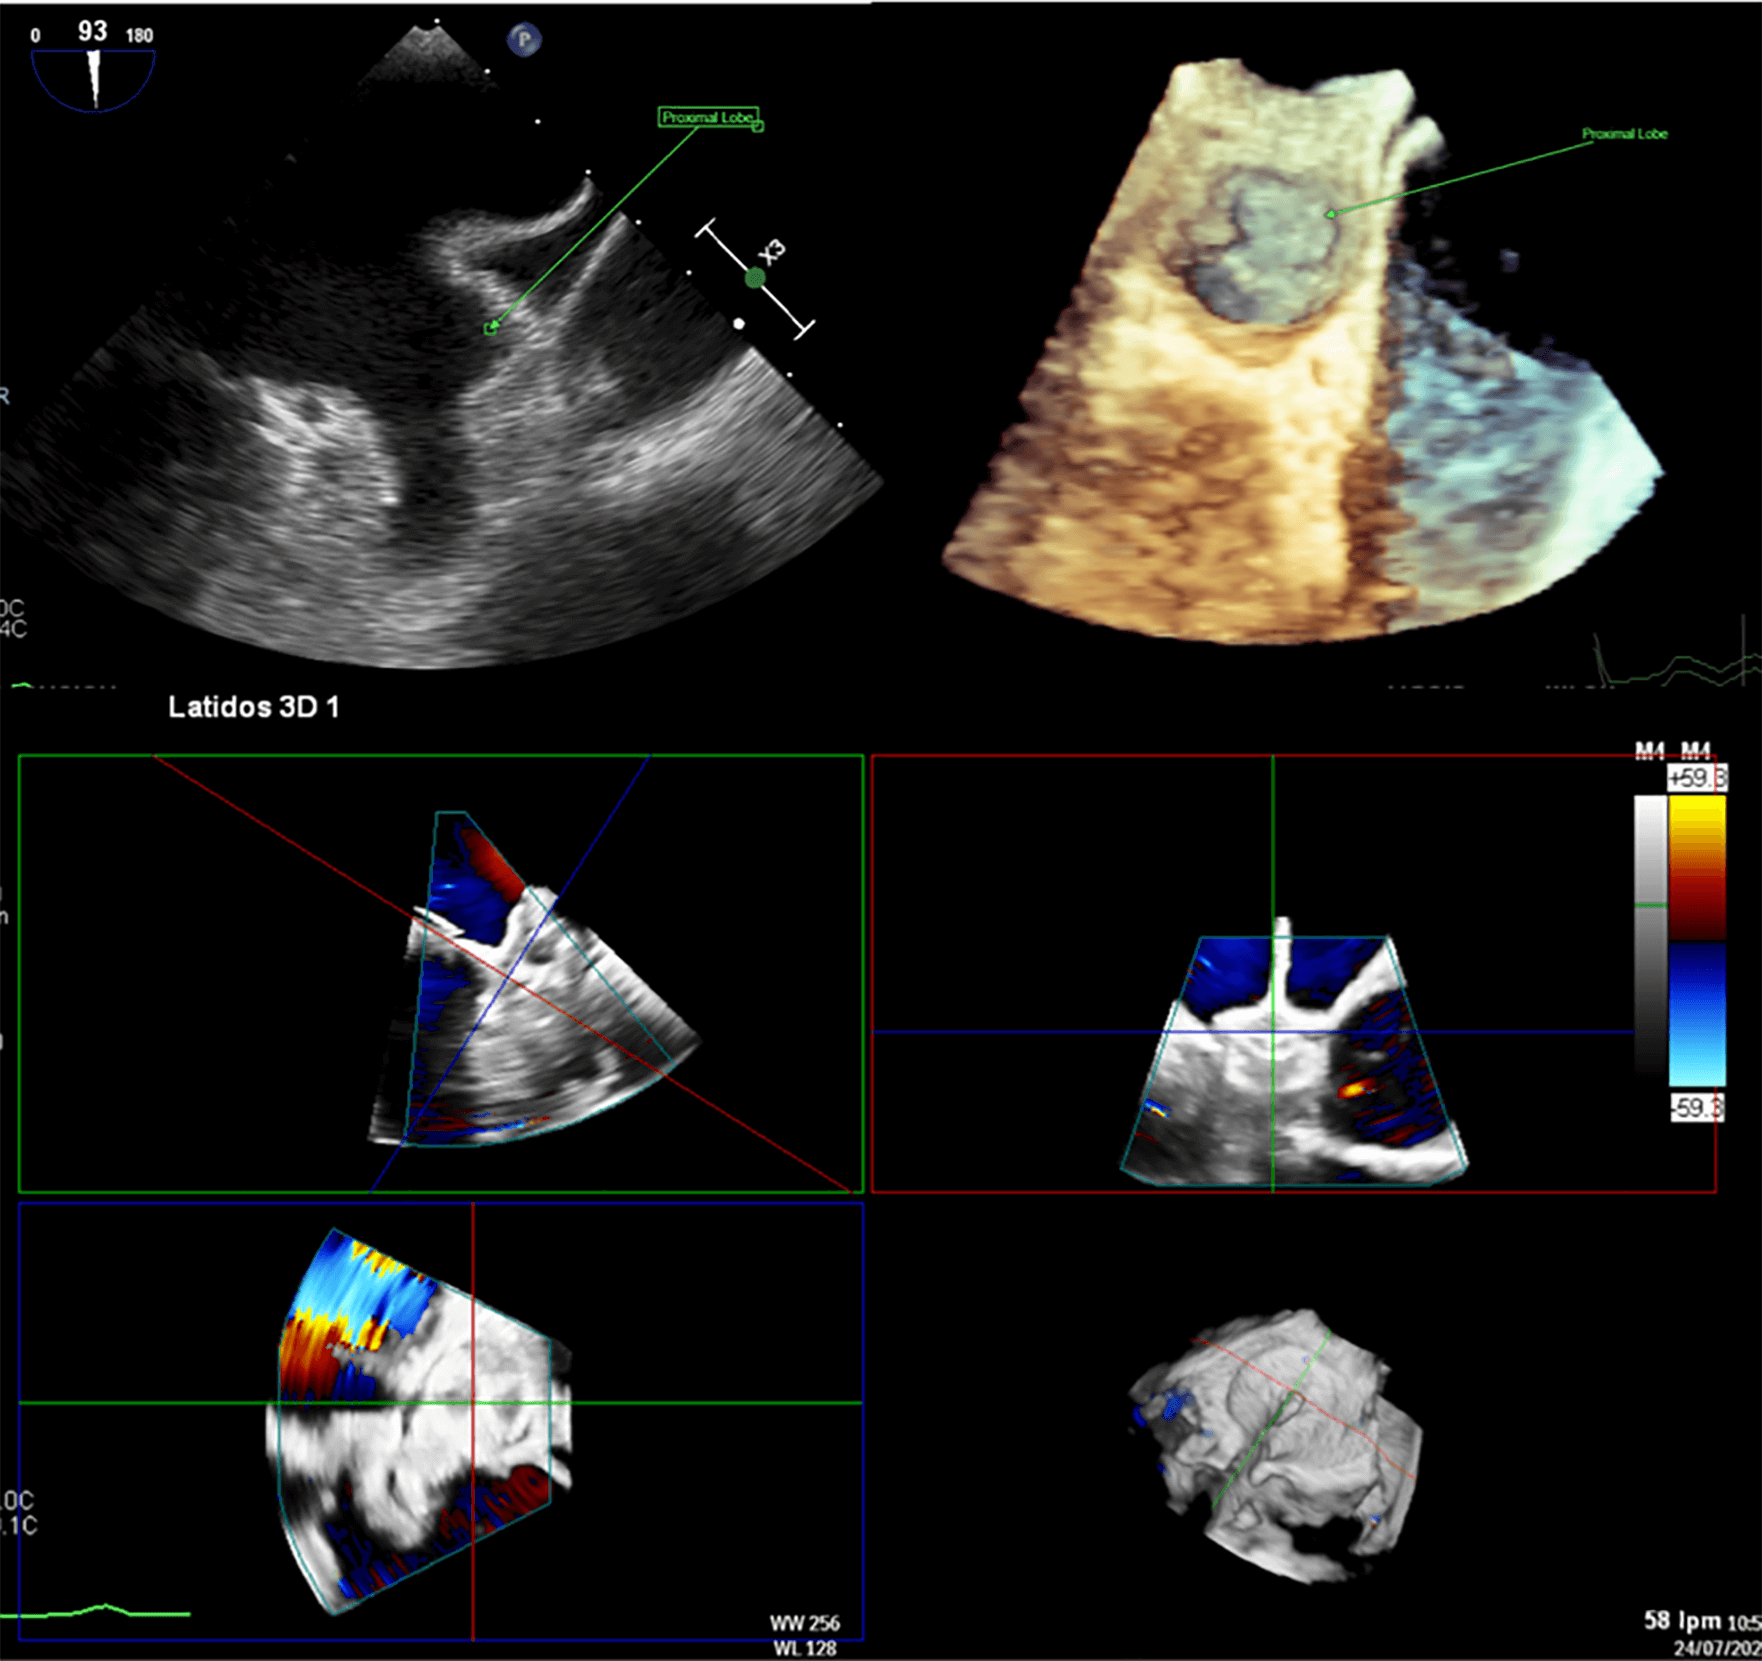

The LAA is separated from the left superior pulmonary vein (LSPV) by the Coumadin ridge, an endocardial fold that externally corresponds to the ligament of Marshall. The LAA may have one or more lobes or protrusions, which are extensions of its functional portion [17]. Based on cardiac computed tomography (CCT) findings, Wang et al. [18] classified the LAA into four main morphologies: windsock, cauliflower, cactus, and chicken wing (Fig. 2). The authors also described the spatial relationship between the LAA and the LSPV, categorizing it as high type (superior to the LSPV), a mid-type (parallel to the LSPV), or a low type (inferior to the LSPV). Among these, the chicken-wing morphology is the most common variant and is generally considered the most challenging for percutaneous closure due to its broad ostium and shallow depth. Conversely, the cauliflower morphology has been most frequently associated with embolic events [16, 19].

Fig. 2.

Anatomic variant of the left atrial appendage (LAA) depicted by transesophageal echocardiography (TEE). (A) Windsock; (B) Chicken wing; (C) Cactus; (D) Cauliflower.

Of note, the current morphological classifications have demonstrated limited predictive value for procedural complexity and clinical outcomes in LAAC [18]. Therefore, additional anatomical and functional parameters should be considered during preprocedural planning, as discussed later in this review.